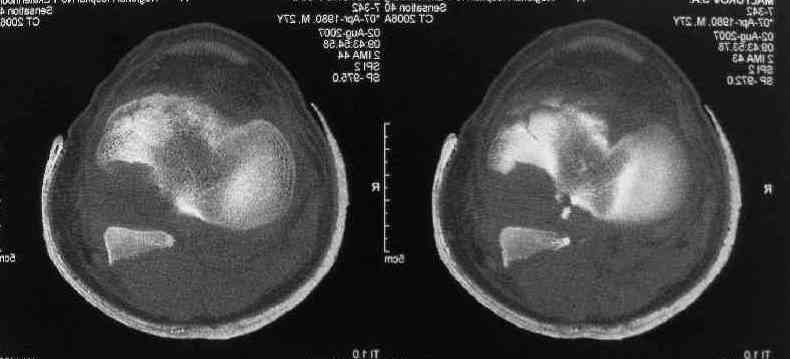

Based on the images ( it would be nice to have axial cuts),it seems to be posteromedial fragment, almost all the way into

posterior portion of the tibial eminance.

I thank for attaching the CT scan. it makes all the details very clear.

the approach should be standard posterior one (same that we use to fix the avulsed PCL).

the fragment is rotated and hence may require some manipulation, especially in flexion of the knee joint.

fixation may be with cancellous screw and washer.

Операция из разряда травматологической "экзотики" прошла успешно. Доступ понравился:анатомичный, хорошая визуализация, удобно работать и оператору и ассистентам. Наложили пневможгут, но воспользовались им только на этапе ревизии сустава. Фрагмент развернулся на 90 град. на 2-ух "жгутах": медиально - сухожилие m.semitendinosus, латерально - задняя крестообразная связка. Мобилизовали,развернули и уложили на место без особого труда. Фиксировали отмоделированной 1/3-трубчатой пластиной. Мениск оказался неповрежден. Сустав стабилен. Обошлись без

иммобилизации, планируем начать ранние движения. Остальное на фото, дополнительно приложены корональные срезы КТ.